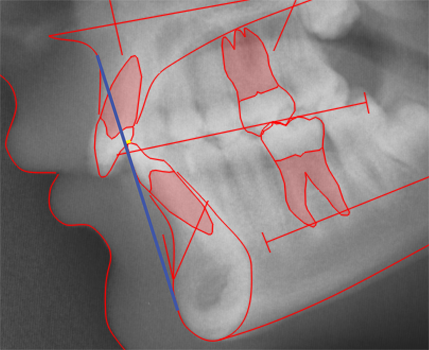

CEPHALOMETRIC MORPHOLOGICAL ANALYSIS

The illustations on this introduction page are discussed in detail in:

Cephalometric Morphological Analysis Parameters

Jens Bjoern-Joergensen, DDS, TIOPS ApS, Roskilde, Denmark

Ib Leth Nielsen, DDS, Division of Orthodontics, University of California, San Francisco

Example of variable values calculation sheet